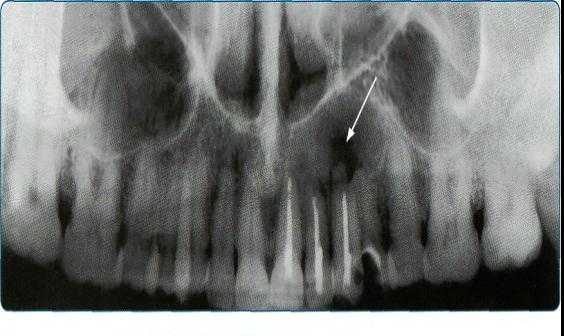

Ортопантомограммы демонстрируют взаимоотношения зубов верхнего ряда с дном верхнечелюстных пазух и позволяют выявить в нижних отделах пазух патологические изменения одонтогенного генеза.

Компьютерная томография широко используется при распознавании заболеваний лицевого черепа и зубочелюстной системы: патологии височно-нижнечелюстных суставов, врожденных и приобретенных деформаций, переломов, опухолей, кист, системных заболеваний, патологии слюнных желез, болезней носо- и ротоглотки.

Метод позволяет разрешить диагностические затруднения, особенно при распространении процесса в крылонебную и подвисочную ямки, глазницу, клетки решетчатого лабиринта.

Карцинома верхней челюсти может прорастать в глазницу, полость носа или решетчатый лабиринт. В этом случае отмечаются рецидивирующие носовые кровотечения, односторонний гнойный ринит, затруднение носового дыхания, головные боли, слезотечение, экзофтальм, диплопия, хемоз. При вовлечении ветвей тройничного нерва беспокоят оталгии.